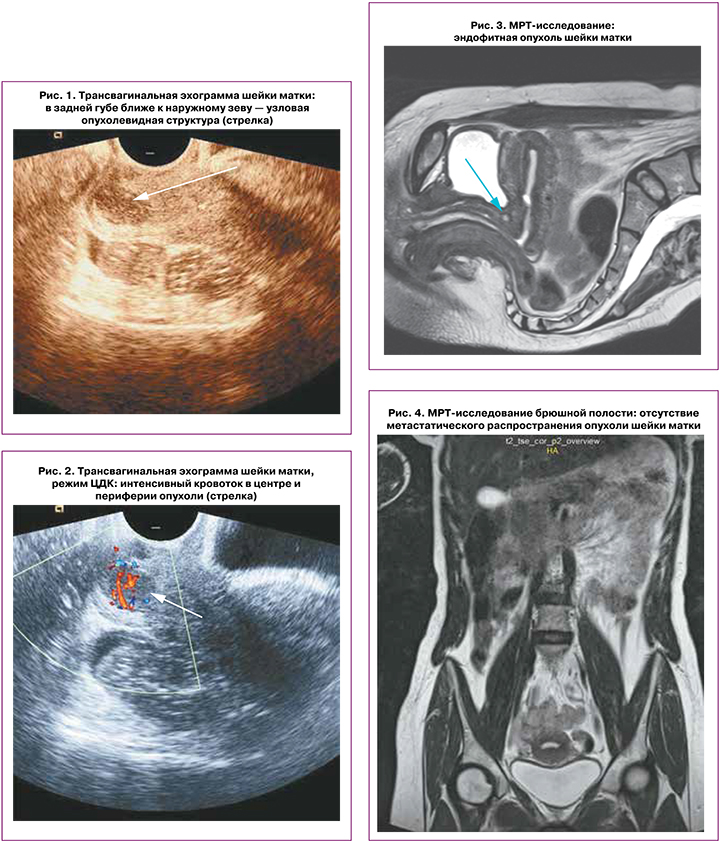

В июле 2021 г. обратилась к гинекологу в связи с ациклическими обильными кровянистыми выделениями из влагалища в течение 3 месяцев. Иных жалоб не было. При трансвагинальной эхографии патологии миометрия тела матки и эндометрия не выявлено. В экзоцервиксе слева в задней губе ближе к наружному зеву визуализирована гипоэхогенная, гомогенная узловая структура с четкими ровными контурами размерами 10×11×14 мм (рис. 1). В нем в режиме цветового энергетического допплера идентифицирован интенсивный низкоскоростной кровоток как в периферических, так и в центральных его отделах (рис. 2). На основании данных эхографии было сформулировано два варианта диагноза: «васкуляризованная миома (?)», «подозрение на РШМ (?)».

Для оценки распространенности опухоли была рекомендована МРТ с контрастированием. МРТ- картина: шейка матки размерами 32×31 мм; по левой полуокружности, по передней и больше по задней губе шейки матки локализована эндофитная опухоль размерами 10×9,5×14 мм (рис. 3), при внутривенном контрастировании активно гетерогенно накапливающая парамагнетик. Распространение опухоли: дистально своды и стенки влагалища представляются интактными; проксимально: распространение до ½ шейки матки, тело матки не вовлечено; МР-признаков распространения на параметрий не выявлено, боковые стенки таза интактны, тазовая брюшина не вовлечена (рис. 4); яичники неизмененной структуры с фолликулами до 10 мм (правый размерами 24×22 мм, левый размерами 18×13 мм), матка в anteflexio, тело размерами 32× 37×34 мм, миометрий не изменен, эндометрий однородный до 3 мм; мочевой пузырь наполнен, внутрипросветных образований не выявлено, мочеточники не изменены, стенки прямой кишки не изменены; увеличенных измененных лимфатических узлов в зоне сканирования не выявлено (N0); поражения костей нет; свободной жидкости в брюшной полости нет. Заключение: МР-картина опухоли шейки матки.